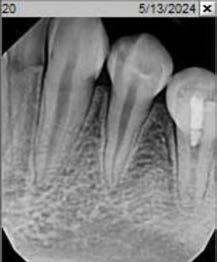

Employing revascularization by infiltrating stem cells from apical papilla and using them to treat immature necrotic tooth with periapical infection promotes root development and reduces fracture risk. Case report.